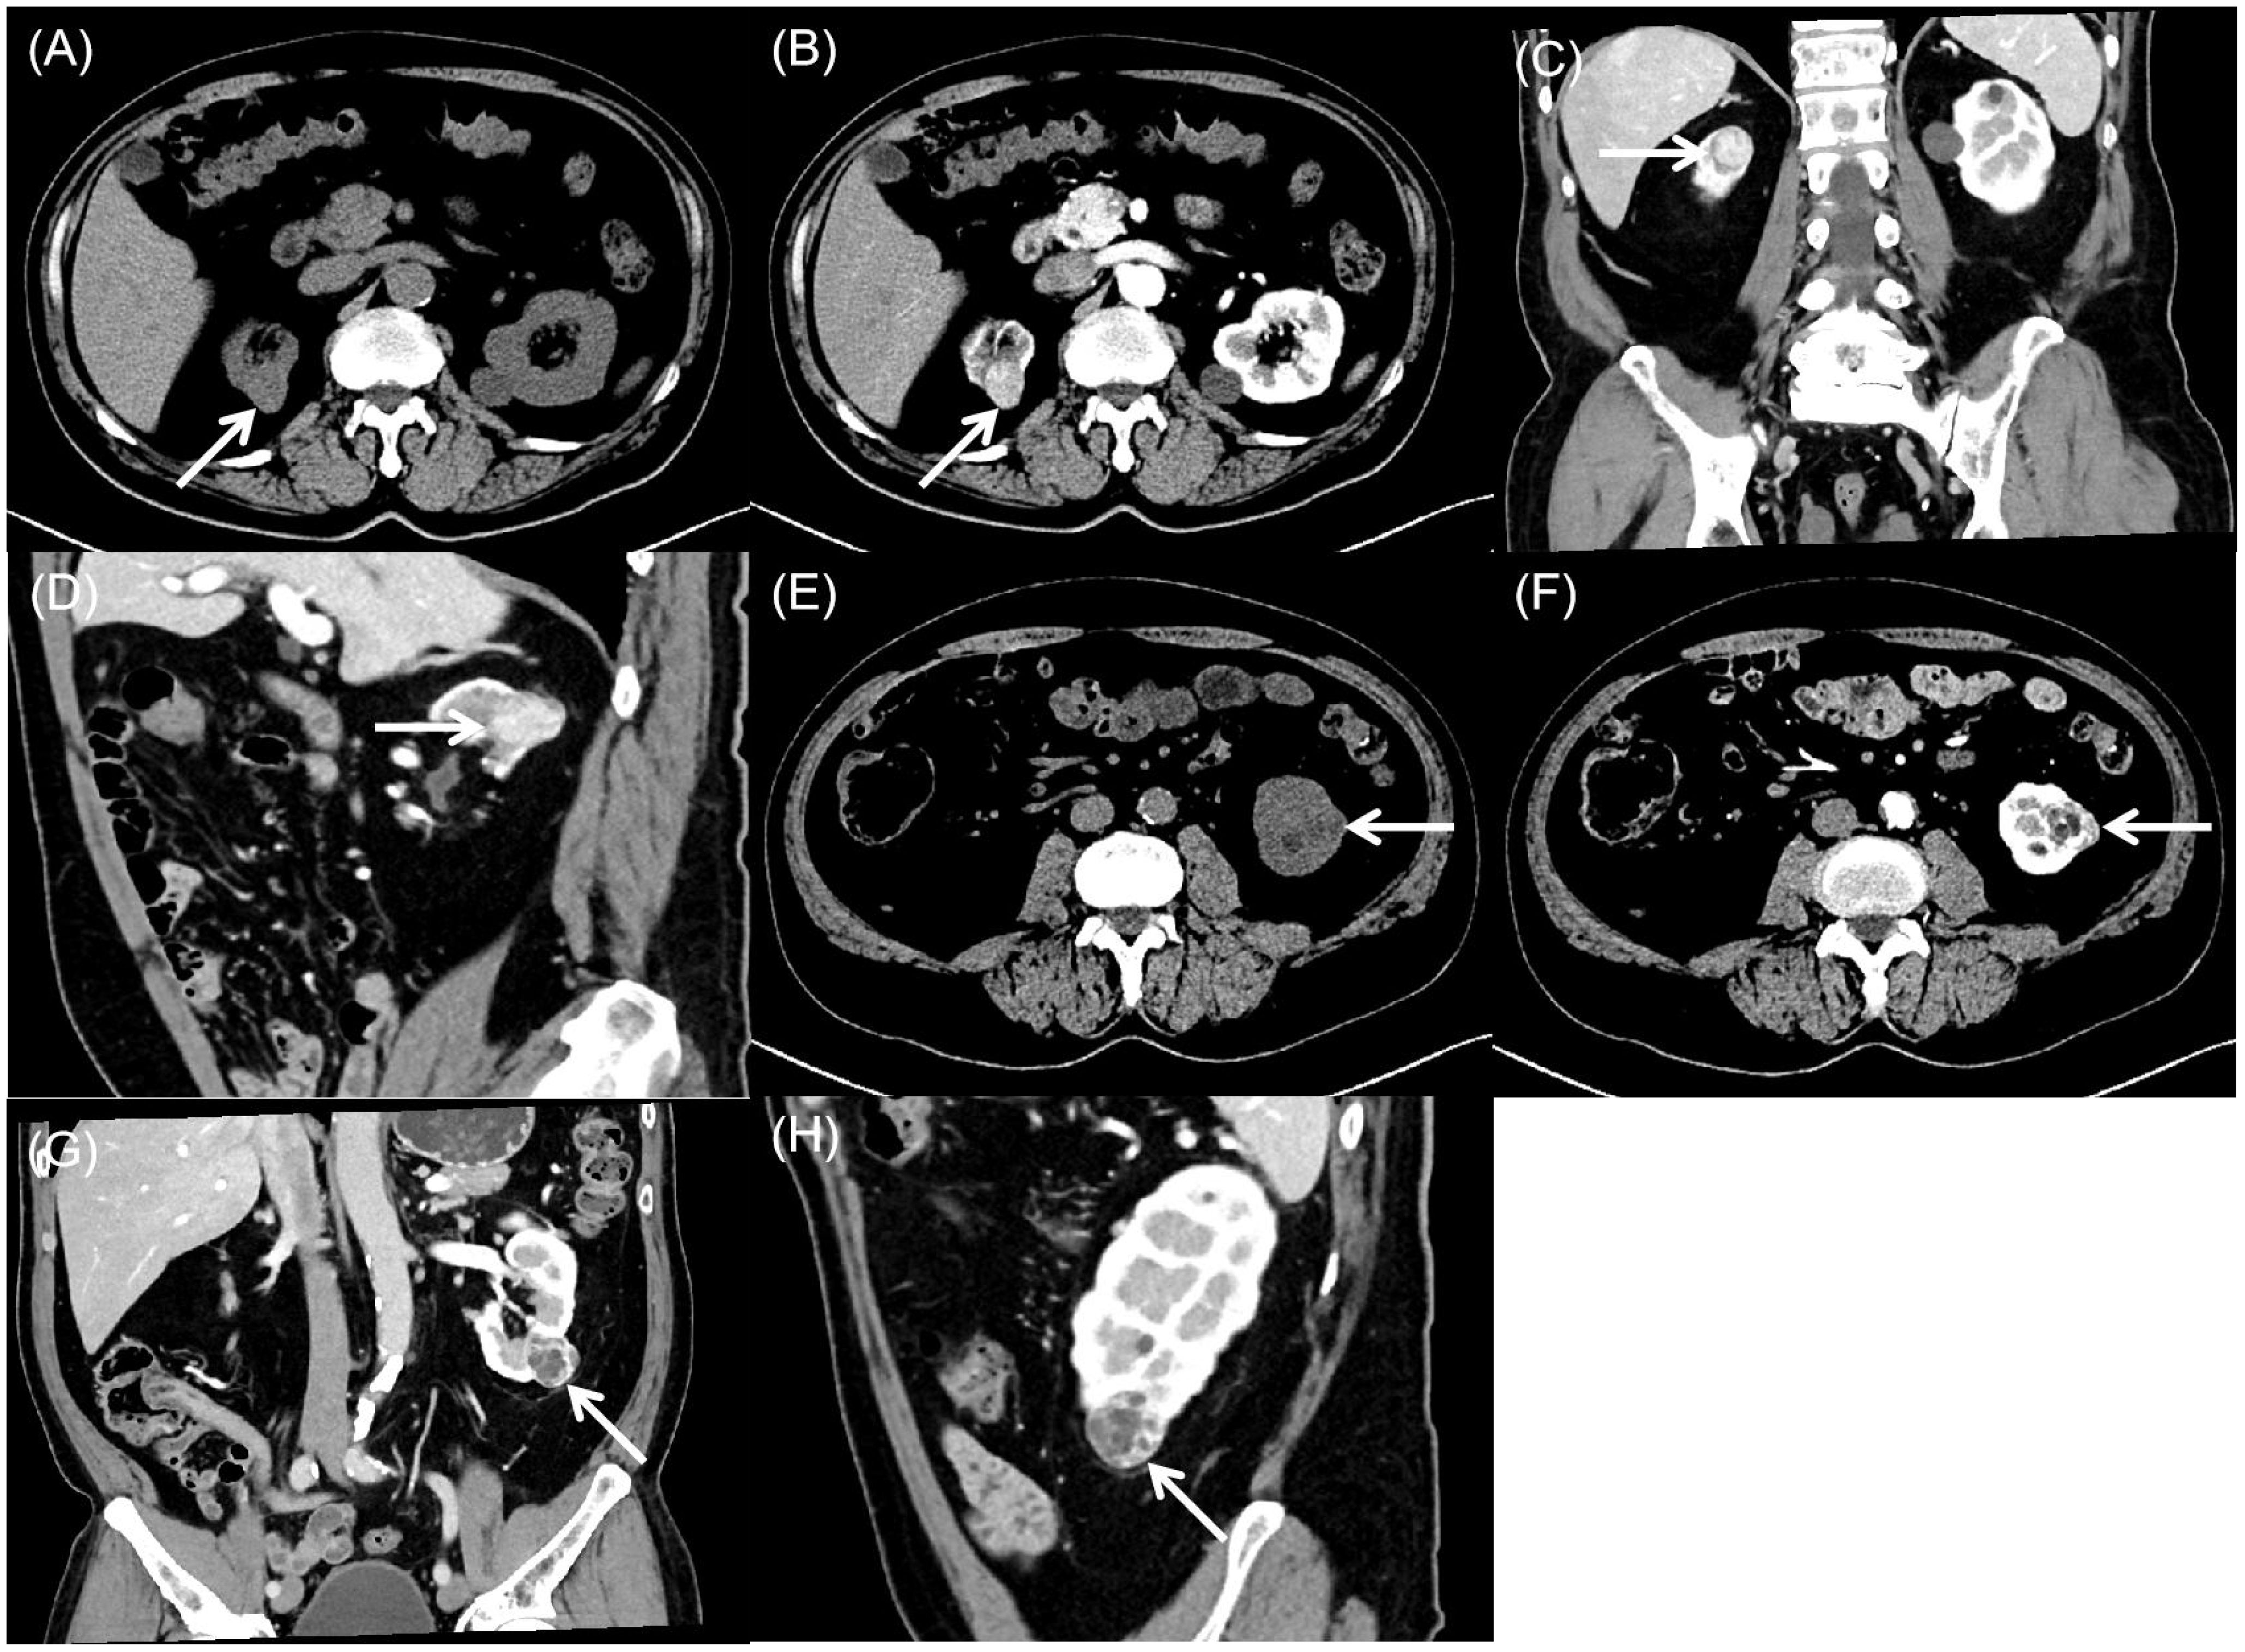

Background: This report presents an exceptionally rare case of bilateral synchronous renal tumors comprising papillary renal neoplasm with reverse polarity (PRNRP) and renal cell carcinoma with fibromyomatous stroma (RCC-FMS) in a single patient. No prior cases of this specific combination occurring synchronously and bilaterally have been reported. Case Presentation: A 65-year-old man presented with incidentally detected bilateral renal masses. Abdominal ultrasound and contrast-enhanced computed tomography (CT) revealed distinct imaging characteristics for each tumor. The right kidney mass was exophytic, heterogeneous, and hypovascular on ultrasound, showing marked heterogeneous enhancement with hypoenhancing foci on CT. The left kidney mass was a well-circumscribed, mixed-attenuation nodule with peripheral/septal enhancement on CT. The patient underwent bilateral laparoscopic partial nephrectomy. Histopathological and immunohistochemical analysis confirmed PRNRP in the right kidney (CK7+, GATA3+, Ki-67 approximately 2%) and RCC-FMS in the left kidney (PAX-8+, CA IX+, CD10+, Ki-67 approximately 3%). Real-time quantitative-PCR testing was positive for a KRAS exon 2 mutation, but was negative for NRAS (exons 2-4) and BRAF V600 (exon 15) mutations. Conclusion: This represents the first documented case of synchronous bilateral occurrence of PRNRP and RCC-FMS. It highlights significant diagnostic challenges due to overlapping imaging features with more common renal tumors. It underscores the critical role of multimodal imaging (ultrasound, CT) combined with meticulous histopathology, immunohistochemistry, and molecular genetic analysis for accurate diagnosis. The generally indolent nature of both tumors supported successful nephron-sparing surgical management. This unique case emphasizes the need for a high index of suspicion for rare tumor subtypes and a multidisciplinary approach to optimize the diagnosis and tailored treatment of complex renal masses.